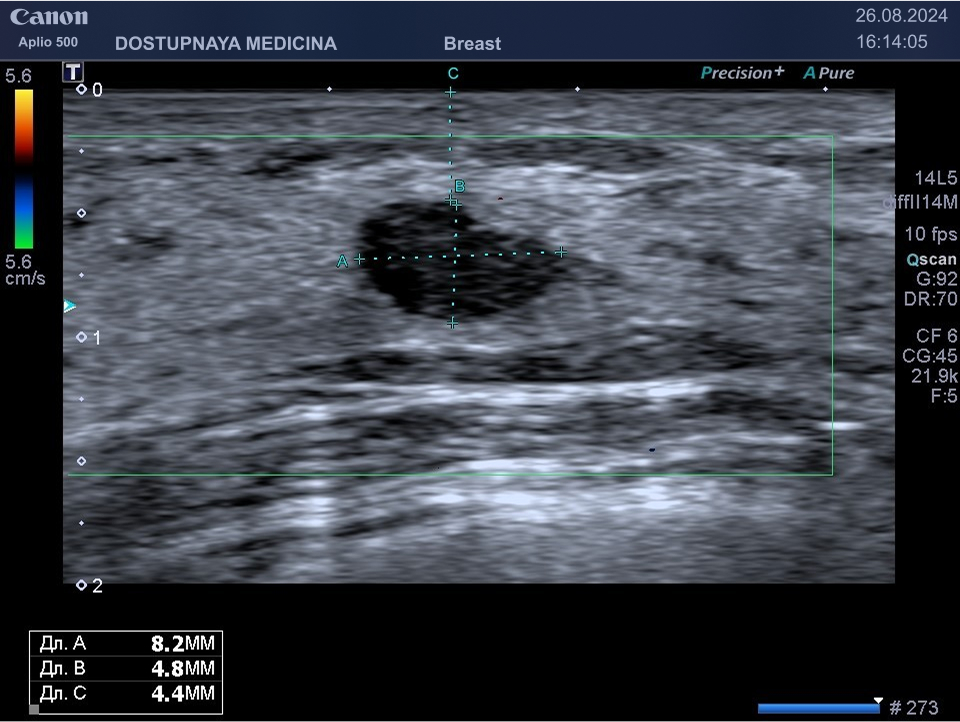

Следует проводить дифференциальную диагностику фиброаденомы с раком молочной железы, с кистой и с цистаденопапилломой. Поэтому важно повторить ультразвуковое исследование через 3 месяца, а затем при отсутствии тенденции к росту опухоли необходим УЗИ контроль через 6 месяцев.

Киста может быть заполнена жидким или густым секретом. Киста с жидким секретом на УЗИ выглядит как анэхогенное (чёрное) образование округлой или овальной формы, киста с густым секретом на УЗИ выглядит как гипоэхогенное (серое) образование.

Встречаются атипичные кисты, содержащие перегородки и имеющие неправильную форму. Такие кисты имеют большую степень онкологической настороженности и относятся к категории BI-RADS3, соответственно требуют более тщательного наблюдения.